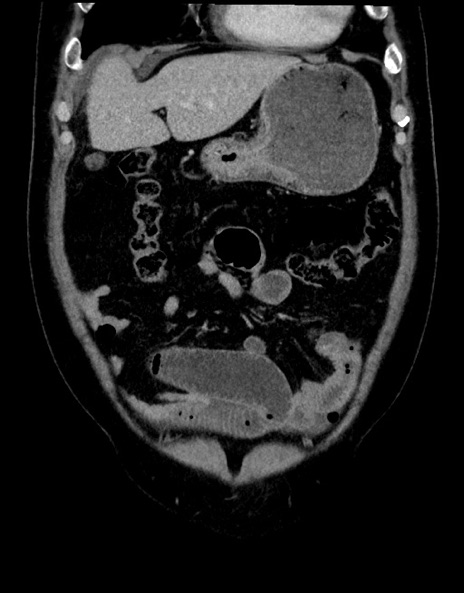

症例15(冠状断像)

【症例】70歳代男性

【主訴】腹痛

【現病歴】今朝から腹痛あり。全体的に痛い。特に左上の方。排ガスが今日はない。冷や汗が出る。

【既往歴】直腸癌術後

【身体所見】左側腹部〜上腹部に圧痛あり。腹膜刺激症状明らかなではない。軽度反跳痛。左下腹部に術後瘢痕あり。

【データ】WBC 7700、CRP 0.02